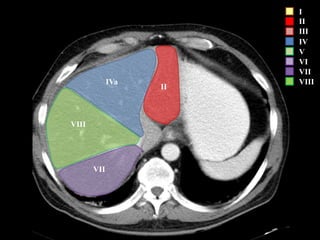

COUINAUD asignó un sistema de numeración para definir la segmentación

hepática.

IVa

VIII

VII

I

II

I – Entre cava y porta

II – el más superior de los izquierdos

III – Por debajo del II

IV – por delante de la vesícula

V – por detrás de la vesícula

VI – relación con riñón derecho

VII – el más posterior de los segmentos superiores

VIII – domo hepático

Las claves de la segm. Hepática